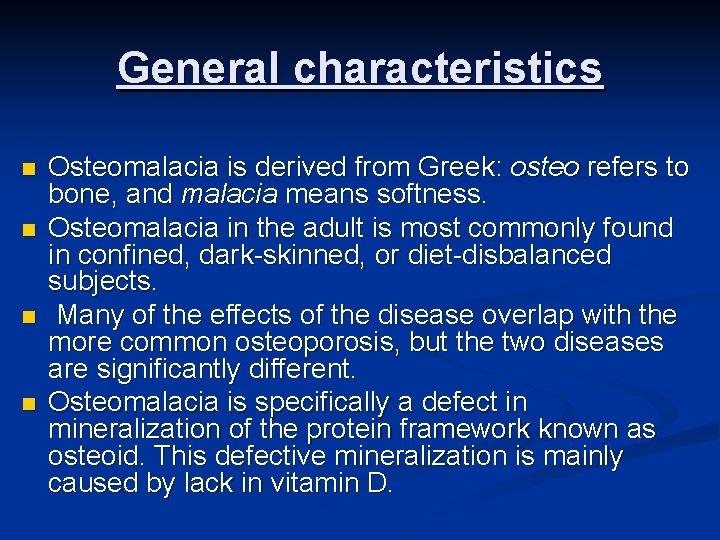

General characteristics n n Osteomalacia is derived from Greek: osteo refers to bone, and malacia means softness. Osteomalacia in the adult is most commonly found in confined, dark-skinned, or diet-disbalanced subjects. Many of the effects of the disease overlap with the more common osteoporosis, but the two diseases are significantly different. Osteomalacia is specifically a defect in mineralization of the protein framework known as osteoid. This defective mineralization is mainly caused by lack in vitamin D.